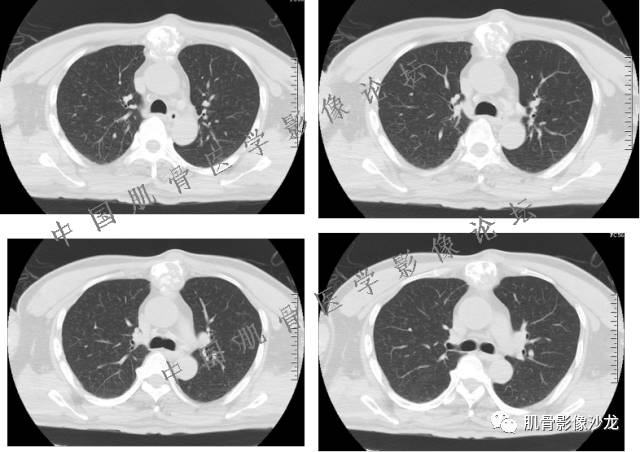

1、软骨肉瘤可以有膨胀性骨质破坏(病例3,4),可以有溶骨性骨质破坏(病例2),局部皮质因为破坏变薄,中断 ;

2、软骨基质T2WI高信号,软骨小叶分叶状,也就会出现高老师提到的骨内膜扇贝形压迹。一般认为骨内膜扇贝形压迹超过骨皮质厚度的2/3是软骨肉瘤在长管状骨的特征性表现。如上图。3、软组织肿块或肿胀;

4、 钙化,环形,弓形,边缘模糊 ;

5、增强后进行性延迟,不均匀分割状强化, 会强化的纤维间隔,软骨小叶不会强化,关于老师们说到的钙化,软骨肉瘤不一定会有钙化 。

雪舞 :1、骨恶性肿瘤的发病率排名:多发骨髓瘤、骨肉瘤和软骨肉瘤

2、软骨肉瘤的发病部位排名:最好发部位为髂骨,其次股骨、肱骨和脊柱。

3、软骨小叶的详细解释:

郝大鹏: 软骨小叶常规时间不强化,延迟几个小时会强化。常规时间内强化的是小叶间隔